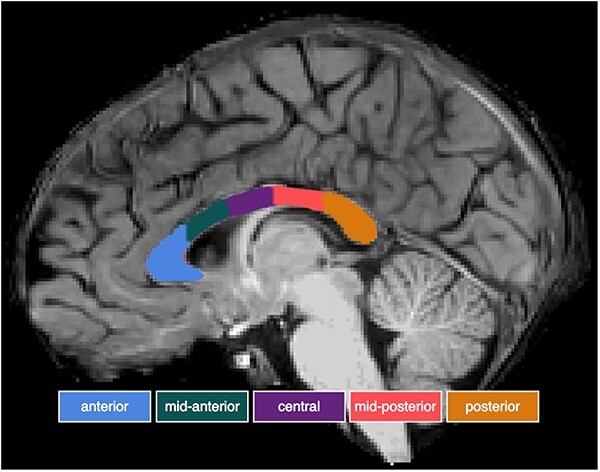

Das Corpus Callosum stellt den wichtigsten interhemisphärischen Trakt der weißen Substanz dar und spielt eine wichtige Rolle bei der neuronalen Interaktion zwischen den Hemisphären. Es wird angenommen, dass das Corpus Callosum die Sprachfähigkeiten beeinflusst, indem es an der Entwicklung der funktionalen Netzwerkorganisation beteiligt ist. Wir interessieren uns für die spezifische Rolle des Corpus Callosum in der funktionellen Organisation zwischen den Hemisphären vom fetalen Stadium bis zum Erwachsenenalter. Zu diesem Zweck erforschen wir die strukturelle und funktionelle neuronale Konnektivität und Sprachentwicklung bei Kindern mit Corpus Callosum Agenesie. Darüber hinaus untersuchen wir den Zusammenhang zwischen Sprachfähigkeiten und neuronalen Merkmalen des Corpus Callosum bei Kindern mit typischer Entwicklung.